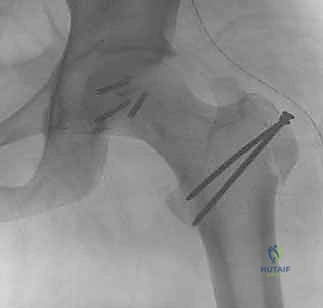

3. التثبيت الداخلي المفتوح (ORIF - Open Reduction and Internal Fixation)

بعد الوصول إلى الكسر وتنظيف المفصل من الشظايا والدم المتخثر، يتم إرجاع القطعة المكسورة لمكانها. يستخدم الدكتور هطيف أحدث التقنيات لتثبيتها:

* مسامير هيربرت أو المسامير الغاطسة (Headless Compression Screws): يتم إدخال هذه المسامير بحيث يغوص رأس المسمار بالكامل تحت مستوى الغضروف المفصلي. هذا يضمن عدم احتكاك معدن المسمار بالتجويف الحقي أثناء الحركة، مما يمنع تدمير المفصل.

* الدبابيس القابلة للامتصاص الحيوي (Bioabsorbable Pins):